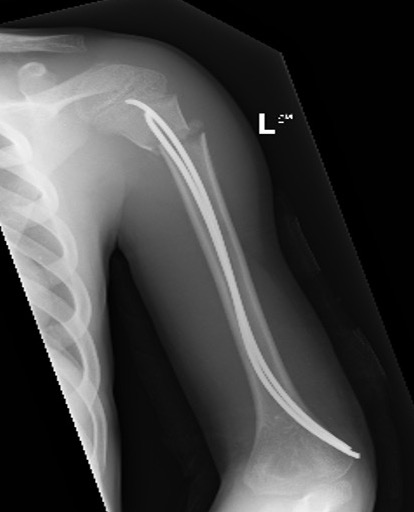

Case: 18 year old boy

Initial xray 18 month xray

Retrograde flexible nails

Surgical technique TENS proximal humerus PDF

Youtube surgical technique TENS proximal humerus video

Technique

2 x drill holes in lateral supracondylar ridge

- 1 cm proximal to lateral epicondyle

- pass 2 x TENS

- standard 0.4 of diameter of bone

- usually 2.5 mm

Results

Marengo et al. J Paediatr Orthop 2015

- 14 patients average age 10 years treated with retrograde flexible nails

- no loss of position, no growth arrest